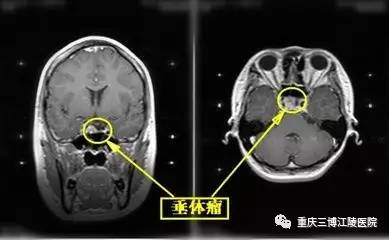

2017年3月16日 垂体瘤稍增大

3月16日,程先生在重庆知名三甲医院行复查MRI示垂体瘤稍增大,未做特殊处理。